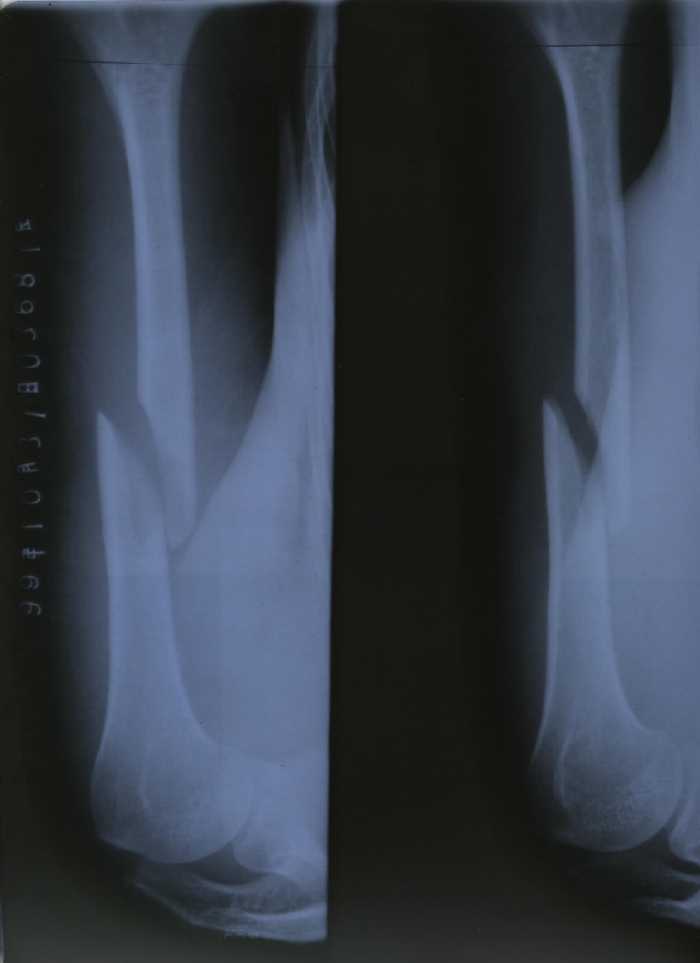

进京上访被打致骨折(附图片)

【明慧网1999年11月2日】 我是浙江省海盐县法轮大法弟子项进英,10月25日进京上访遭公安毒打,左胳膊肱骨骨折。

1999年10月25日,我们一行三人去天安门广场,准备上访。在广场被警察无故拦住盘问:是不是炼法轮功的。我们给予肯定的回答,就被带到附近的一个派出所,那里已经有五六十名大法弟子。登记时我们只回答自己是大法弟子。大家齐背“论语”。警察把十几人拖出,戴上手铐。(一手从肩膀下去,另一手从背后上来的那种很难受的铐法。)警察还让我们跪着,把头往墙上撞。在被铐住的情况下,一个警察还用力反复抻拉我的胳膊,听到胳臂“咔嚓”的一声,我疼得头上直冒冷汗,我知道这是自己的业力,默默忍受着。十五分钟左右,警察见我脸色不对,没有任何声响,就将我的手铐拿下,还晃晃胳膊看是不是装的,又怀疑是脱臼,装了几次但没装上。后来我们被卡车拉至北京城区的一个大院。从车上下来被审讯,然后又被送上车。审讯时一回答是大法弟子就遭毒打。我们被下车、审讯、上车两次。被脱衣服搜查后于10月26日一点左右送至看守所。检查时发现我的胳膊伤势严重。 26日早上一医生来查,当问我的名字我回答是大法弟子时,他就不看了。 27日带我去医院拍片:肱骨骨折,连医生都十分惊讶。30日上午又带我去医院拍片,几个医生会诊说要动大手术。我不愿意做手术,他们就用夹板把我的胳膊绑上,固定后再次拍片,因被强行矫正片子看似正常。警察将前后两张不同的片子均带回。当日下午又提审我, 让我回家,我被海盐公安局警察带回招待所。后找机会出去。现在全国云游。

1. 项进英左臂肱骨骨折后的X光检查结果

2. 当值医生为项进英检查后所写诊断书

(注:从照片和X-ray片看,这位弟子遭打的胳膊应有小血管的破裂。)